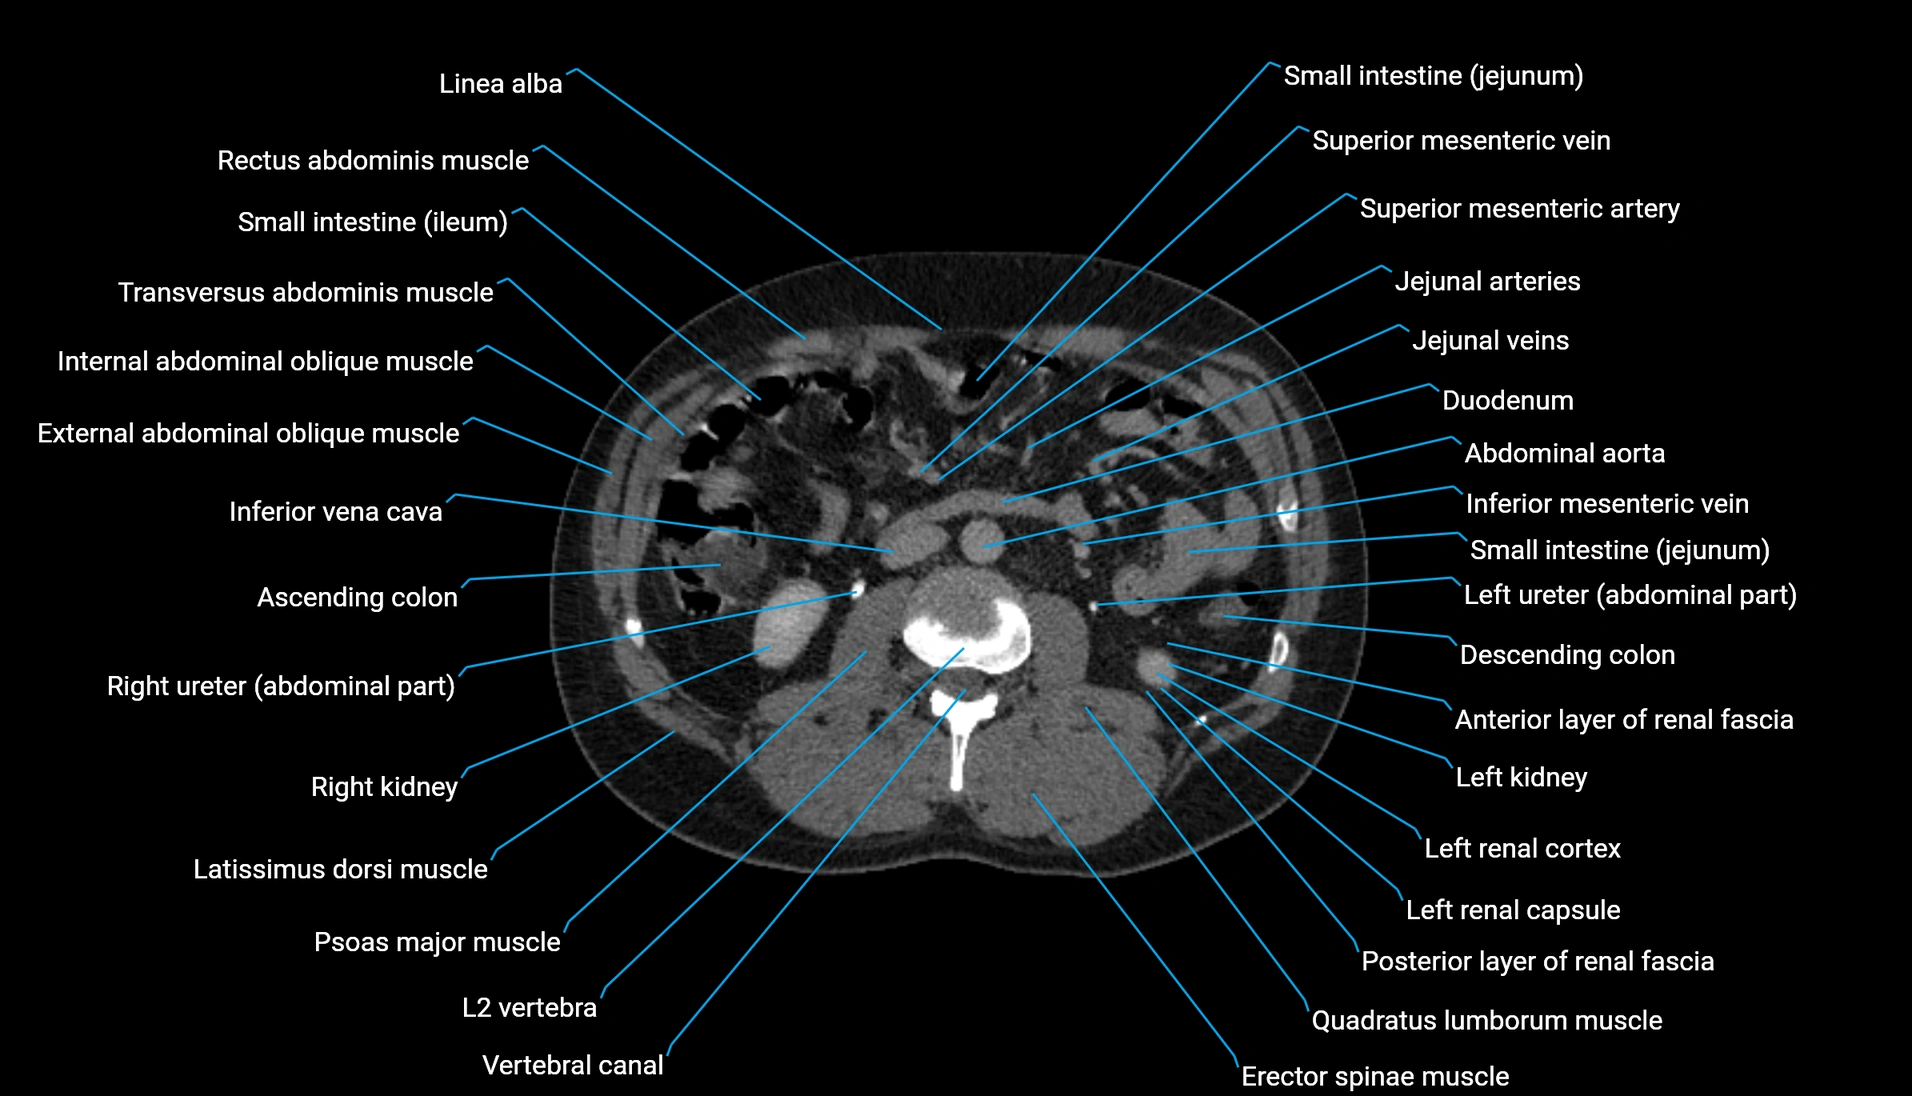

CT Appearance

Non-contrast CT:

-

Demonstrates cortical bone of acetabular rim in excellent detail

Detects fractures, dysplasia, retroversion, or bony overcoverage (pincer impingement)

3D reconstructions used in preoperative hip surgery planning

CT VRT 3D image

CT image